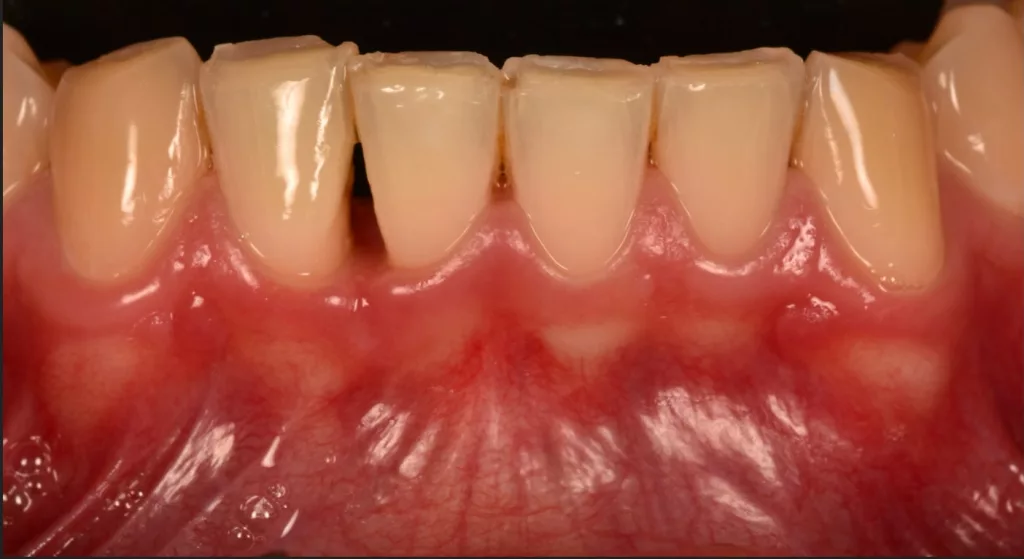

La gingivite se caractérise par une atteinte de la gencive sans atteinte de l’os sous-jacent. C’est une inflammation d’origine bactélkrienne déclenchée par la plaque dentaire au voisinage du collet des dents. Les gencives sont rouges, gonflées et peuvent saigner au brossage ou de façon spontanée.